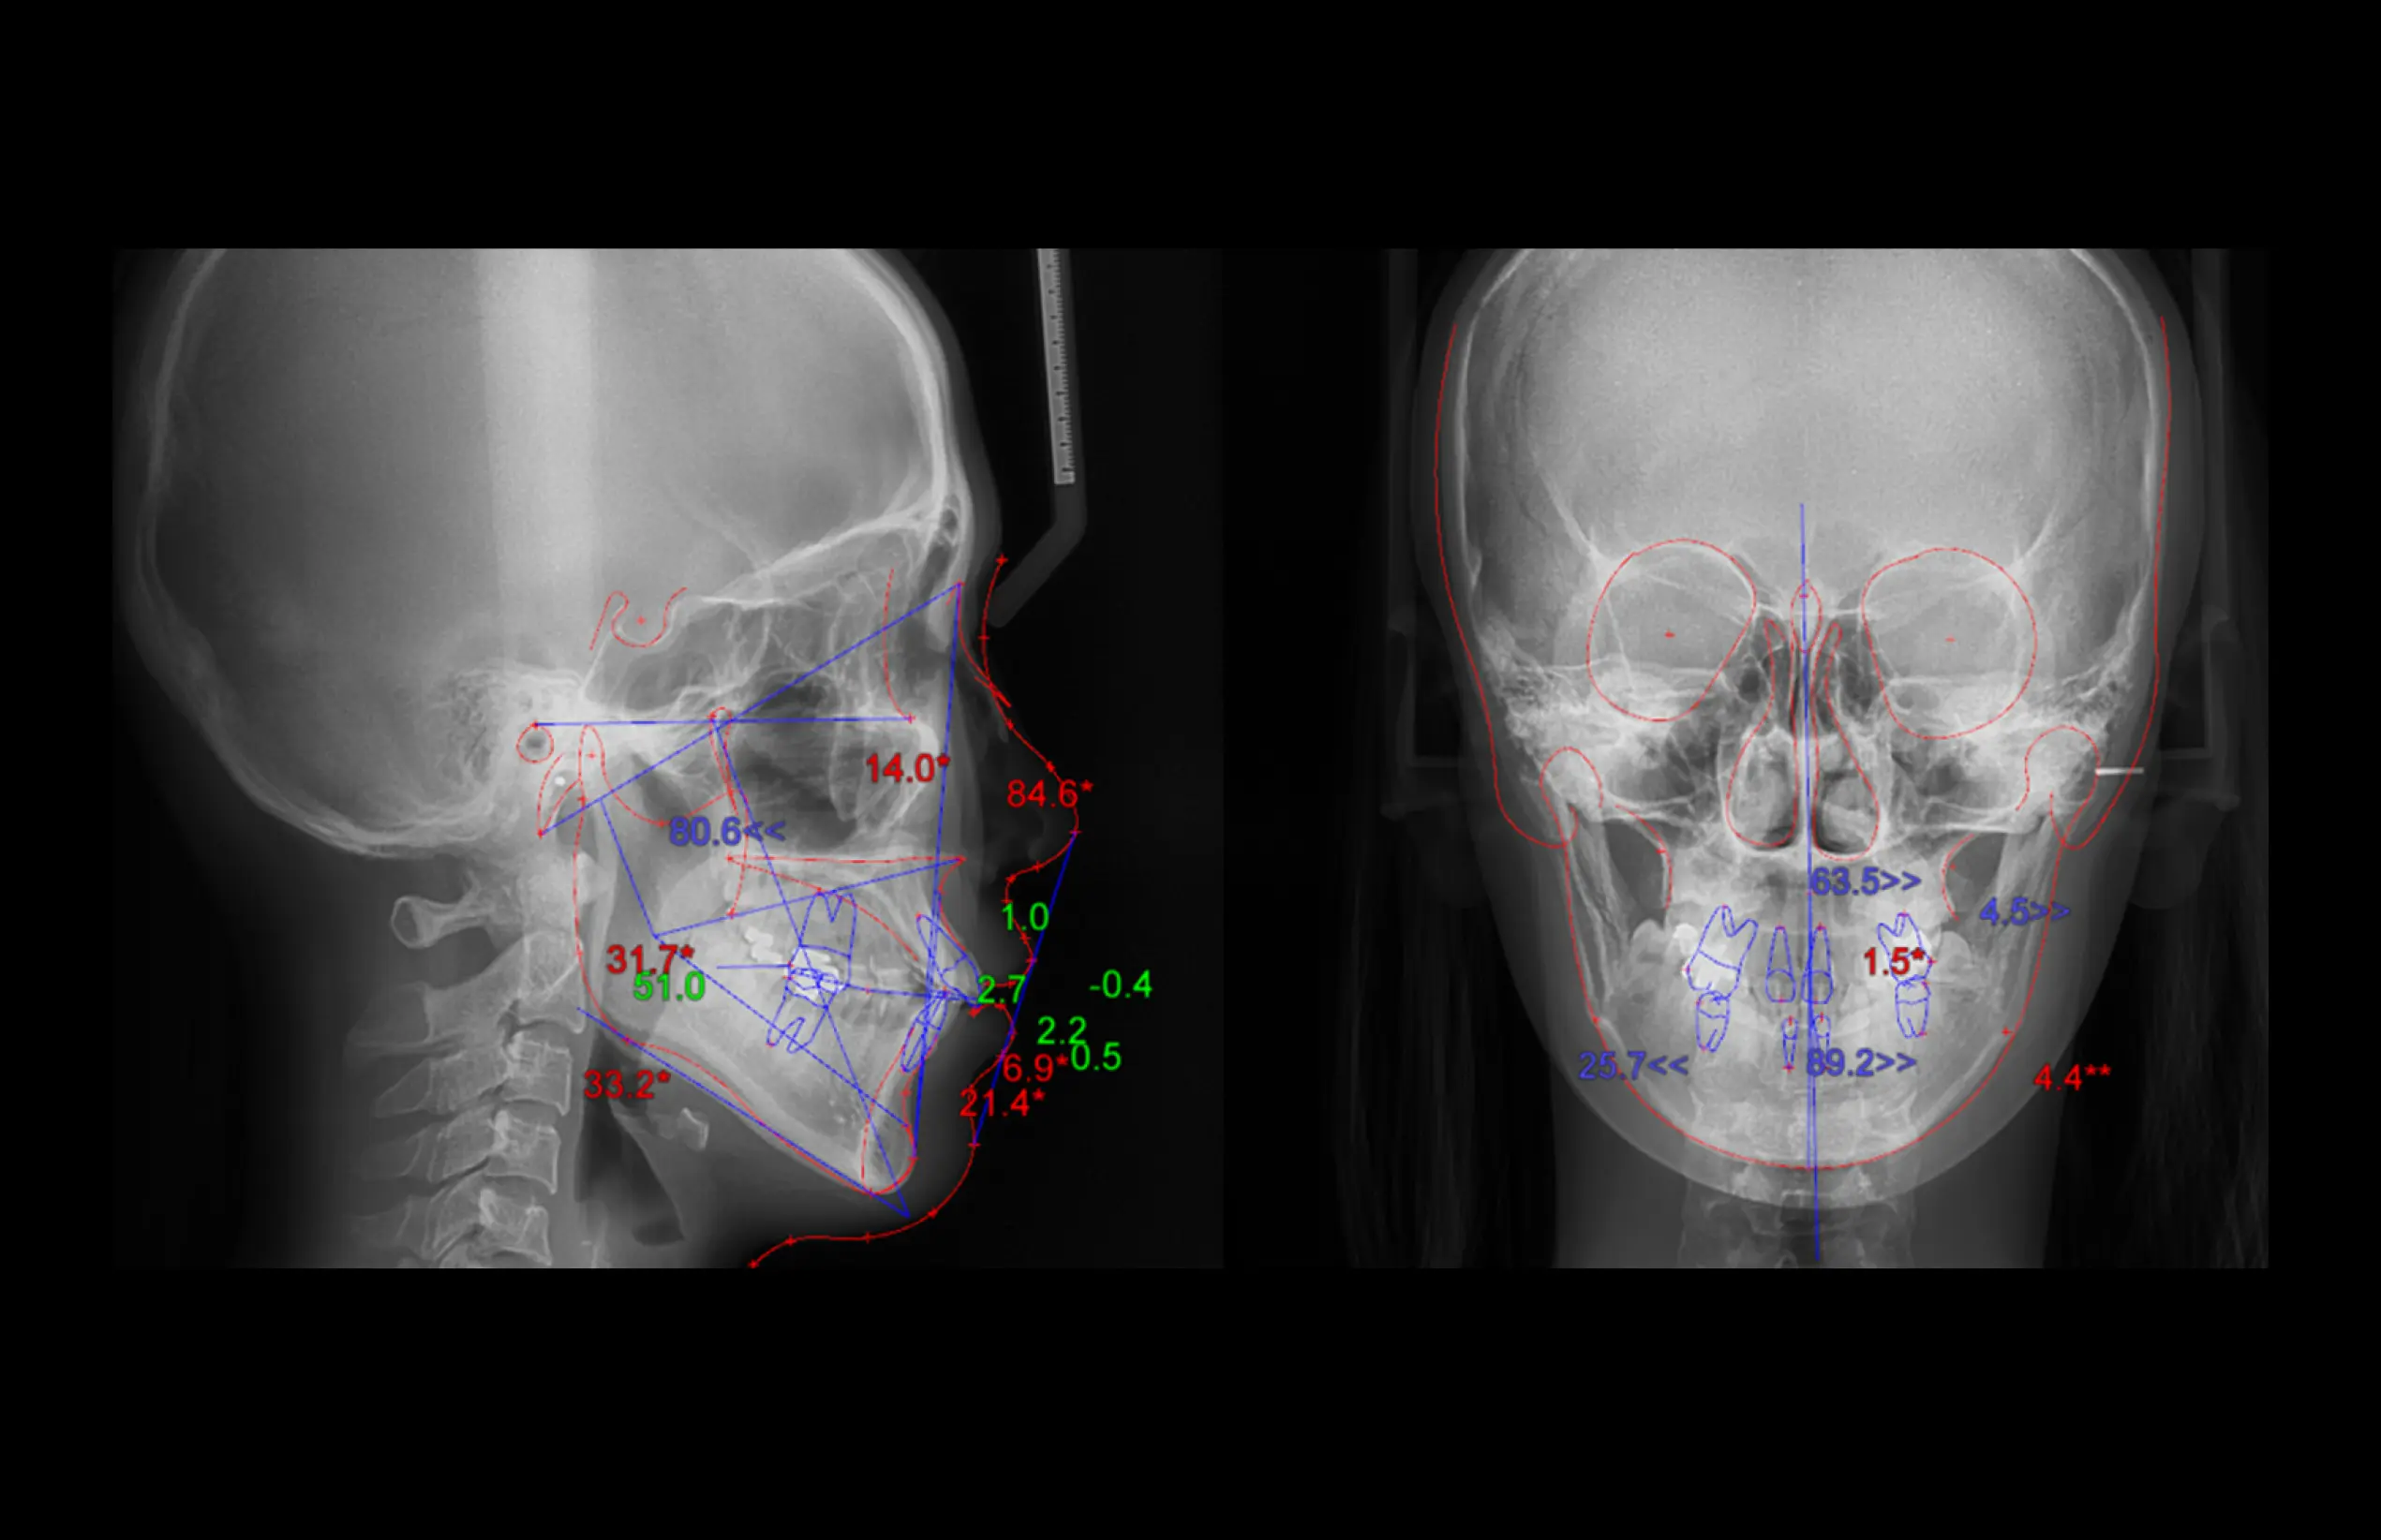

MDSDental Solution

더보기 오토 트레이싱

·환자의 X-ray (측면 & 정면)에서의 디지털

트레이싱

·클릭 한번으로 빠르고 정확한 AI기반의 자동